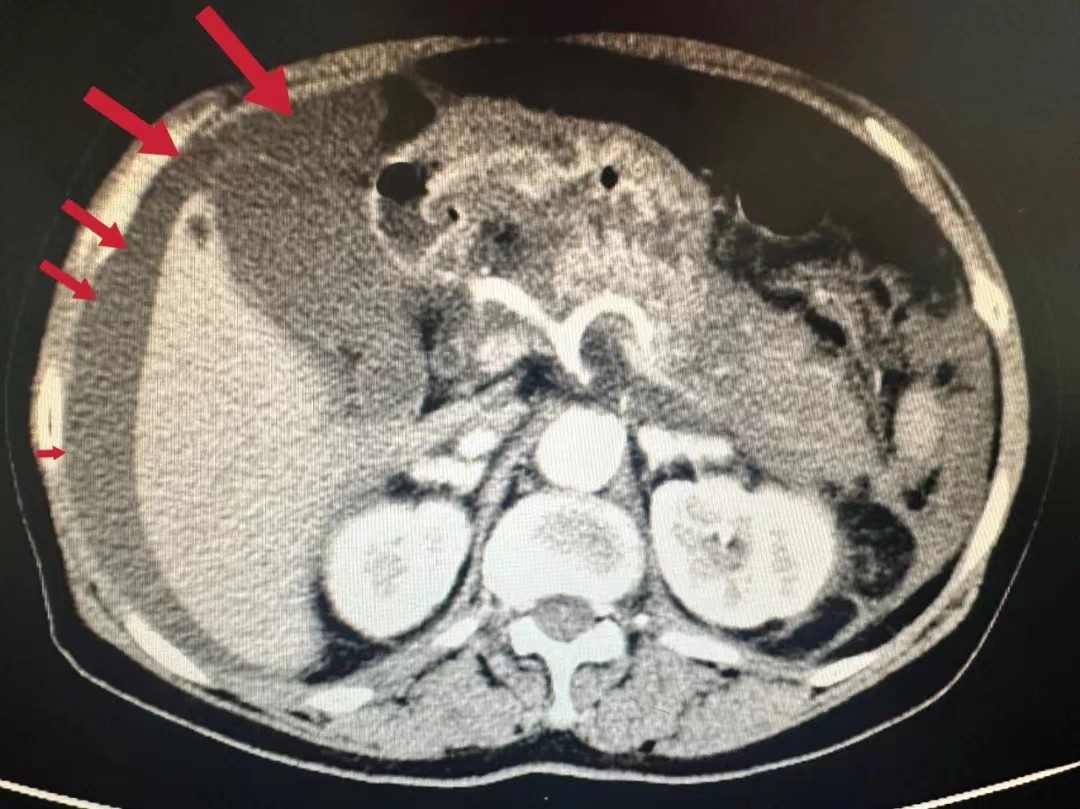

术前CT检查显示黄女士腹腔存在积液

术后CT结果